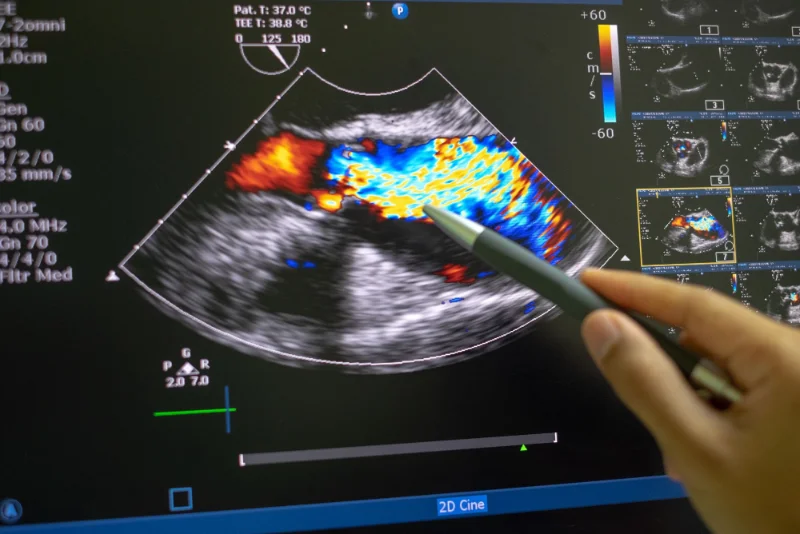

Real-Time Imaging: Ultrasound imaging provides real-time visualization of soft tissues, muscles, tendons, ligaments, and joints, allowing for dynamic assessment of movement and function. This real-time feedback can be valuable for guiding therapeutic interventions and assessing treatment efficacy.

High Resolution: Our advanced imaging equipment produces high-resolution images that allow for detailed visualization of anatomical structures and abnormalities, enabling accurate diagnosis and treatment planning.